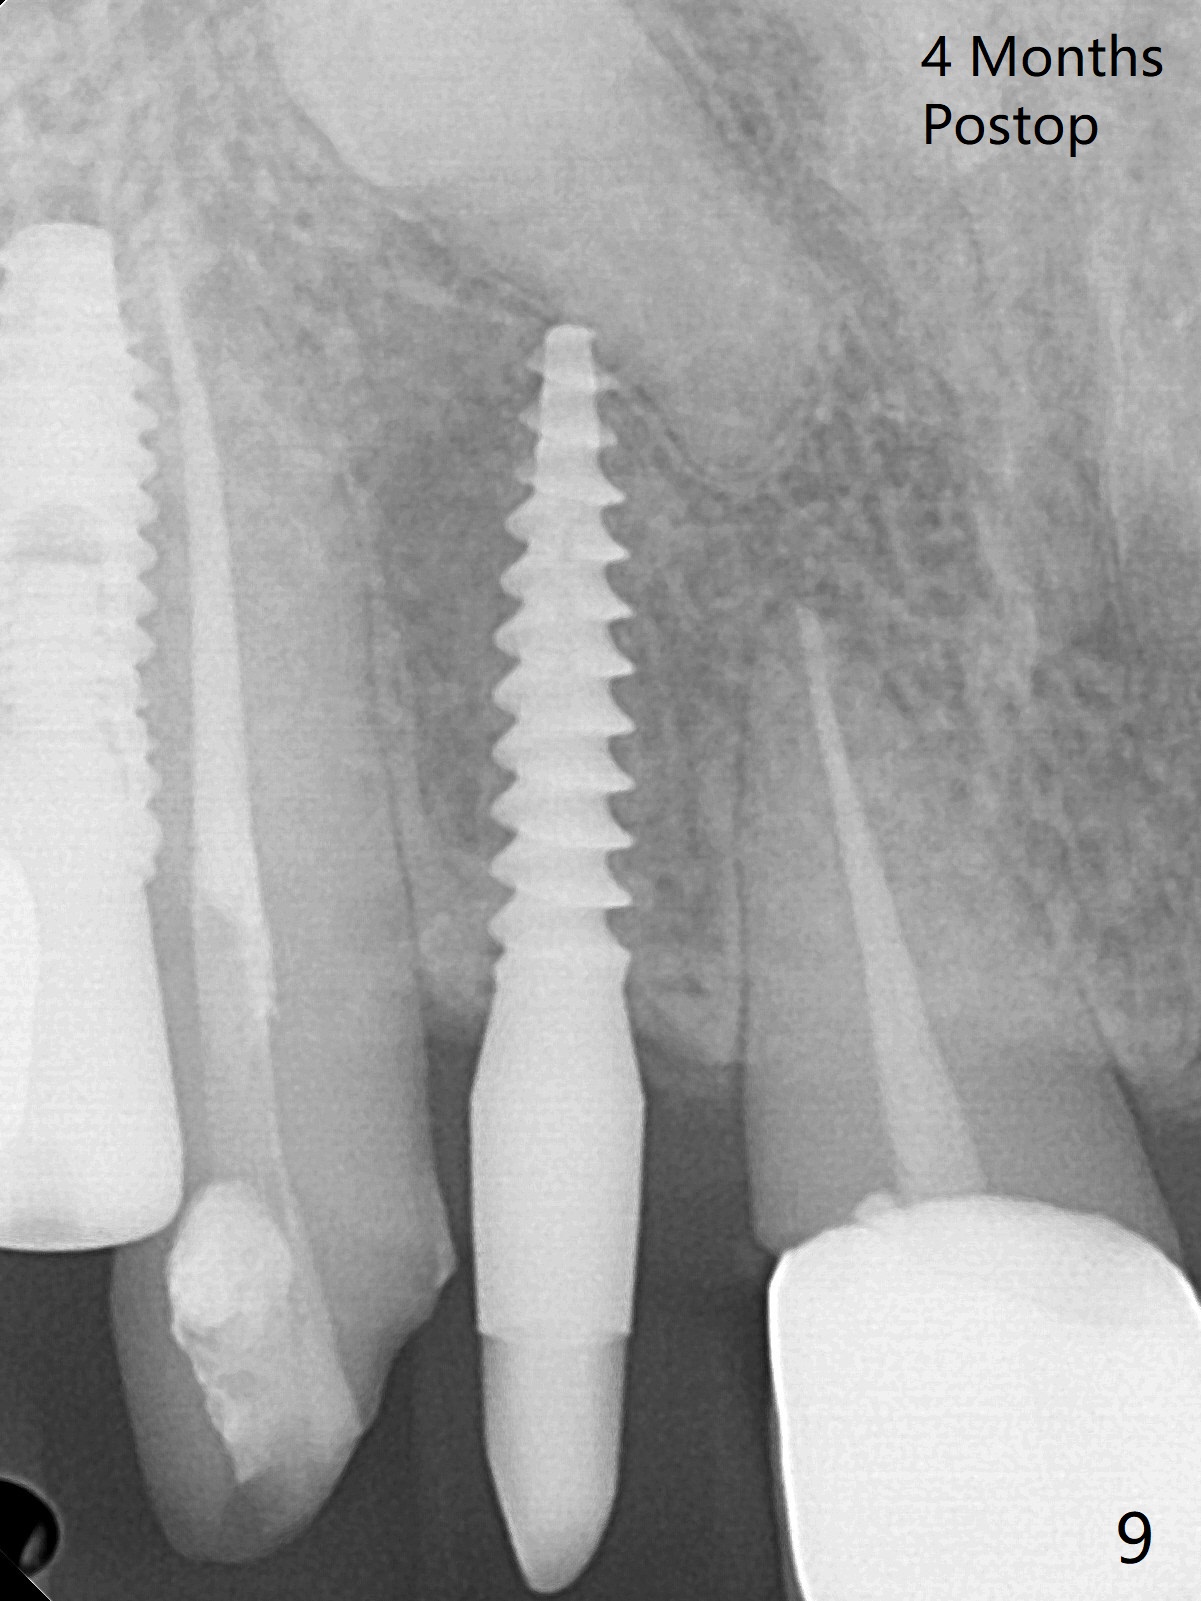

Two of 5x8.5 mm implants are placed at #2 and 3 with sinus lift using water ballooning technique; to avoid invading the neighboring root tips, an intraop PA is taken with a 2.2x11.5 mm drill at #5 (Fig.1). When a 2.5x11.5 mm 1-piece implant is placed at #7, there is 2.4 mm clearance from the impacted tooth (Fig.2). Following 1 mm deeper placement of the 1-piece implant, CT is taken to make sure that the threads are completely covered palatally (Fig.5 P). Interesting is that the sinus membrane is thickened at #2 and 3 (Fig.3 M), as compared to the clear sinus before surgery (Fig.3'). Bone graft is limited in the sinus (Fig.3 arrowheads). The implant at #5 (3.5x11.5 mm) is precisely placed subcrest bucco(B)-palatally (Fig.4). Since the limited field viewed CT does not cover the implant at #2 (Fig.3), immediate postop PA is taken (Fig.6). In fact all of the implants are placed subcrestal, as shown by intraoral X-ray 4 months postop (Fig.7-9). The abutments at #2, 3 and 5 are retorqued (30 Ncm) after crowns' try in and adjustment (Fig.10,11). There is a vertical gap between the implant and abutment at #2 (Fig.11 ^) and a horizontal one at #5 (<). There is apparently no bone loss 1 year 5 months post cementation (Fig.12).